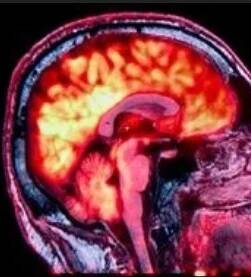

• Een PET-MR scan is een combinatie van een PET scan (positron emissie tomografie) die de doorbloeding of activiteit meet en een MR (Magnetic Resonance). Het tijdseffect van medicatie kan ook met deze techniek nauwkeurig gemeten worden. Bij deze scan wordt ook gebruik gemaakt van onschadelijk radioactief gemerkt suiker.

Er is een mindere stralingsbelasting dan bij een PET/CT scan. De beelden van de PET scan worden boven op de MRI beelden gelegd om tot een nauwkeurige diagnose te komen.

Er zijn helaas te weinig ziekenhuizen die een PET/MR scan aanbieden. Het inzetten van deze techniek vereist een urgente medische situatie. Niet om bewijslast te leveren over langer geleden opgelopen letsels.